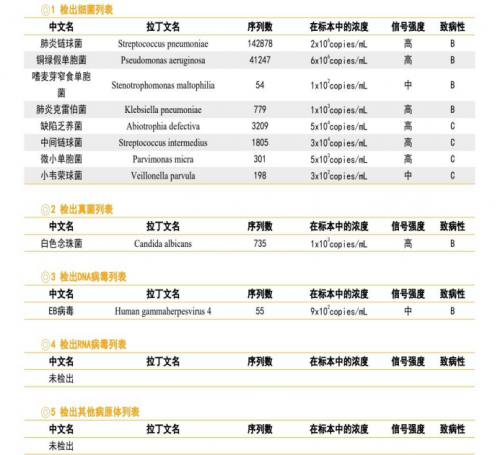

3. EB病毒DNA定量检测、TORCH病毒核酸检测、G试验、GM试验、新冠病毒核酸、呼吸病毒六联检(肺炎支原体DNA、甲乙流、鼻病毒、腺病毒、呼吸道合胞病毒):均阴性。

痰培养结果:

诊疗计划:

1.综合上述辅助检查结果,将治疗方案调整为美罗培南1g Q12H+氟康唑0.1g Qd抗感染治疗。

2.患者肾功能差,肌酐清除率为27.3(CKD4期),暂时未加用复方新诺明抗感染。